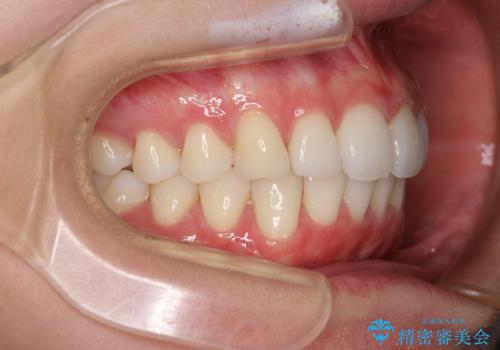

- 上下前歯の叢生を気にして来院された患者様です。

以前矯正をした後戻りということで、歯列不正はそれほど大きくなかったため、インビザライン・ライトを用いて矯正治療を行うこととしました。

前歯のデコボコが残っており、シミュレーション通りに動いていない部分がありましたが、再矯正であることやご本人の満足いくところまでデコボコが改善されたとのことで、治療を終了することとしました。